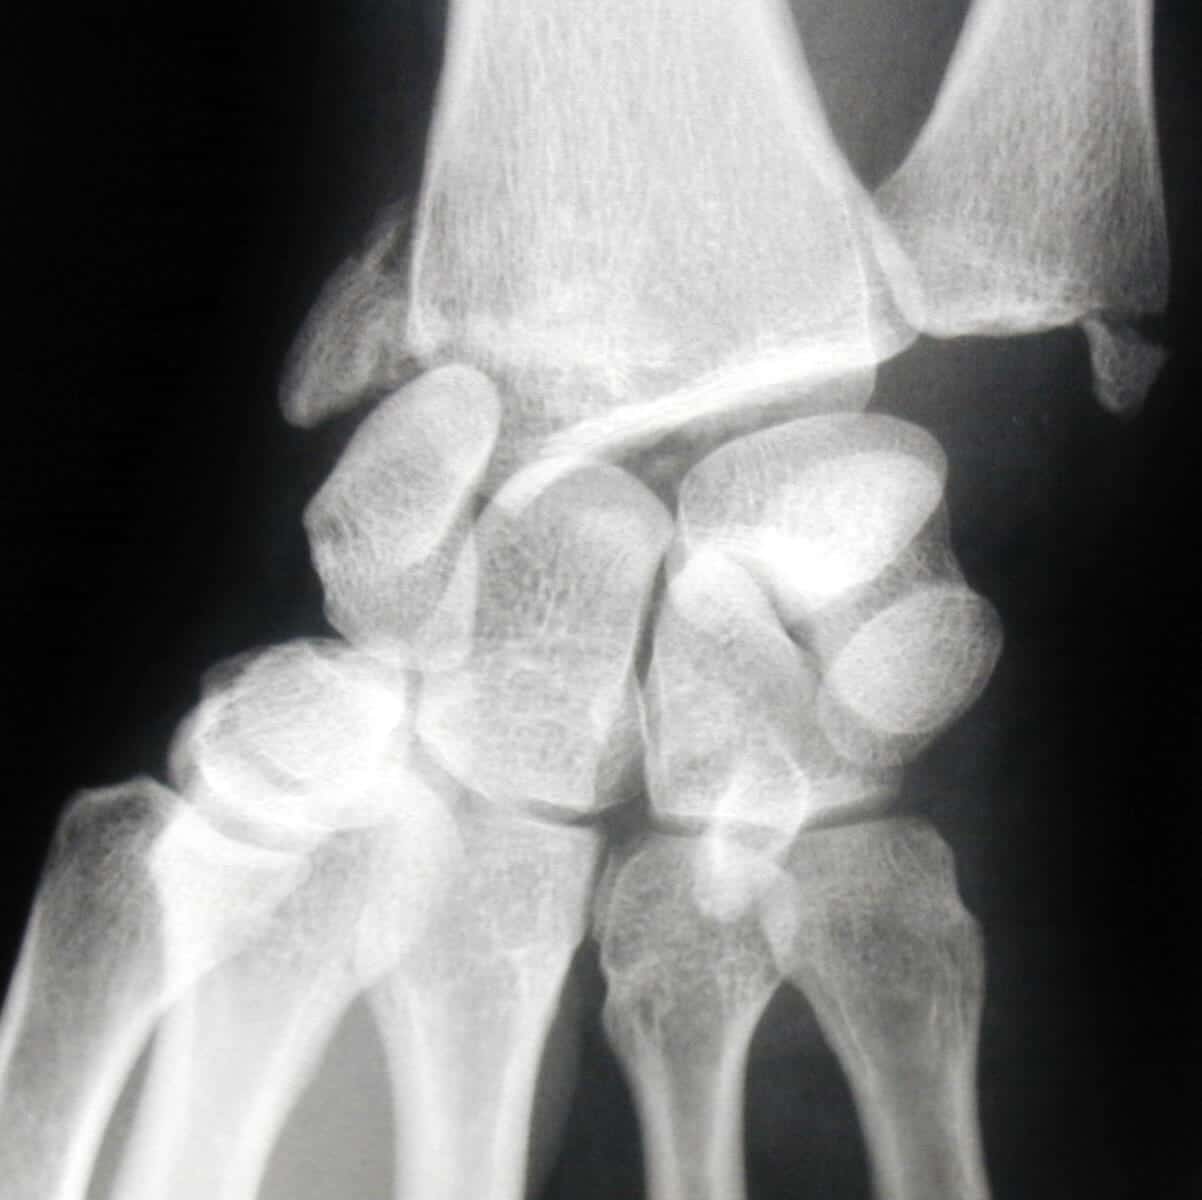

entorse luxation rétro lunaire du carpe

Expulsion du semi lunaire sur une luxation rétro lunaire du carpe